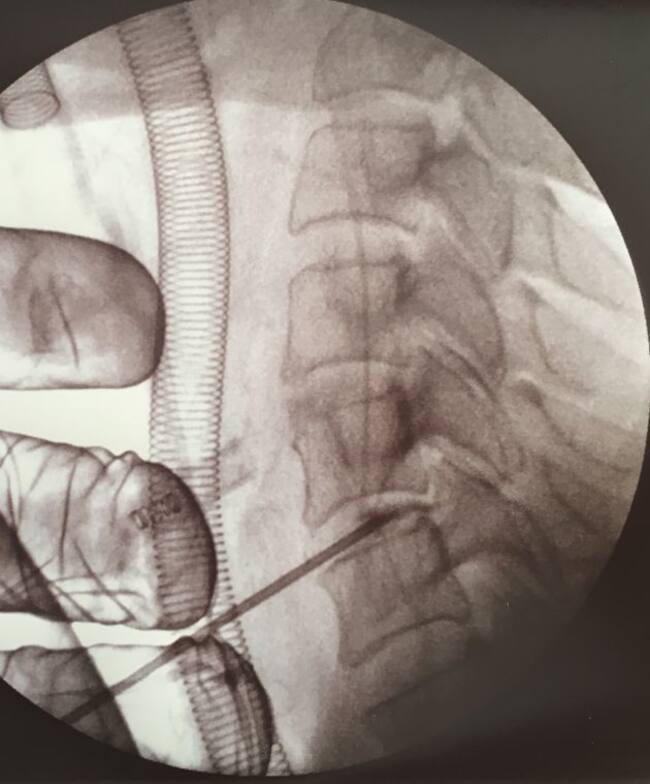

El Centre Mèdic Teknon de BCN ha tractat, per primer cop a l'estat espanyol, una triple hèrnia discal CERVICAL amb cirurgia endoscòpica, a través d'una incisió de 3 mm

En canvi, amb el nou procediment aquests riscos desapareixen. A través d’una incisió mínima (3 mm) s’introdueix l’endoscopi, que porta una càmera incorporada i permet veure totes les estructures amb molta precisió. A més, no secciona teixits sinó que els dilata, sense provocar ferides internes ni sagnat, amb la qual cosa no pot fer-los malbé.